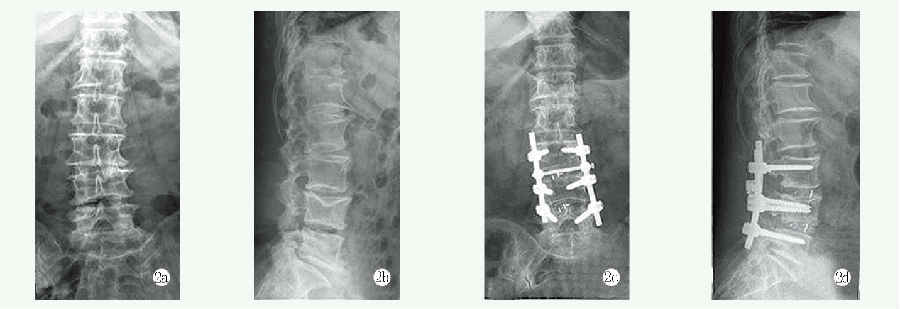

两组影像测量结果见表4,与术前相比,末次随访时两组患者侧弯Cobb 角、C7PL 和SVA 均显著减少(P<0.05)。术前两组间侧弯Cobb 角、C7PL 和SVA 的差异均无统计学意义(P>0.05),末次随访时,长节段组的侧弯Cobb 角、C7PL 和SVA 均显著小于短节段组(P<0.05)。典型影像见图1、2。

图2 患者,女,68 岁,主诉腰部疼痛及麻木,确诊为DS,接受短节段减压融合治疗

2a, 2b: 术前正侧位X 线片显示腰椎侧凸  2c, 2d: 术后正侧位X 线片显示侧凸Cobb 角获得部分矫正